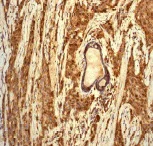

Immunohistochemistry (Formalin/PFA-fixed paraffin-embedded sections) analysis of human liver tissue labelling Cathepsin D with unpurified ab75852 at a dilution of 1/500.

This data was developed using the same antibody clone in a different buffer formulation containing PBS, BSA, glycerol, and sodium azide (ab75852).

Perform heat mediated antigen retrieval before commencing with IHC staining protocol.